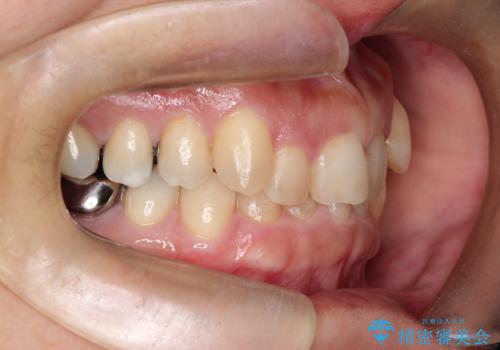

【インビザライン】重度叢生をなおしたい

- 全体的に歯並びをなおしたいことを主訴に来院されました。

上顎前歯が舌側傾斜していたため少し拡大を行いながら非抜歯で治療を行っています。

マウスピースをしっかり使用していただいたので、きれいな歯並びになりました。